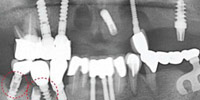

可选方法:种植牙(单颗缺失、多颗缺失及多各牙缺失)、All-on-4种植牙(半/全口牙缺失)、烤瓷牙(个别牙缺失)、活动义齿(全部牙缺失类型)

种植牙(单颗缺失、多颗缺失及多各牙缺失)

All-on-4种植牙(半/全口牙缺失)